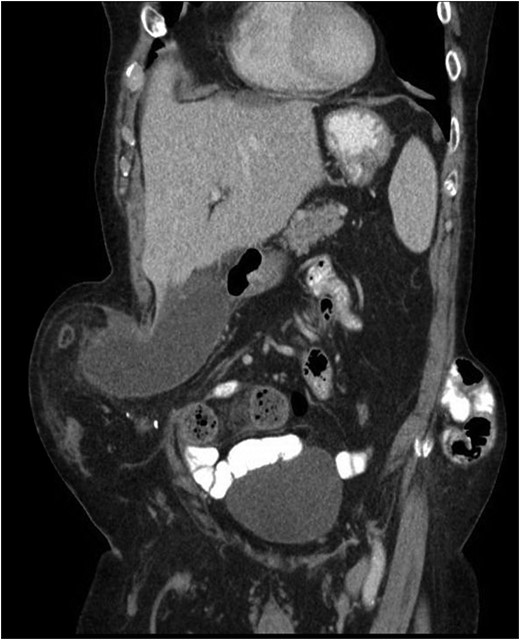

Our patient is an 89-year-old male with a history of a Hartmann’s procedure (2006) for Crohn’s disease of the sigmoid colon followed by a reversal of the colostomy with a diverting loop ileostomy (2008). Due to his comorbidities and age, the patient declined further surgery to reverse his loop ileostomy. Most recently, the patient presented to the emergency room with no ostomy output for the past 14 h, nausea and frequent burping. He reported a burning sensation around his ostomy. His physical examination revealed a large parastomal hernia in the right hemiabdomen and associated tenderness in the right upper quadrant, with no overlying skin changes. His white blood cell count was 8.1 (82.4% neutrophils), and he had normal liver function tests. A computed tomography (CT) scan of the abdomen and pelvis revealed a large parastomal hernia with a wide neck containing a distended gallbladder concerning for acute cholecystitis, as well as a small bowel obstruction with a transition point at the level of the hernia (Figs 1 and 2). A previous CT scan showed the same hernia with a nondistended gallbladder and non-obstructed bowel entering and exiting the stoma (Fig. 3).

CT from current admission with distended gallbladder consistent with acute cholecystitis.